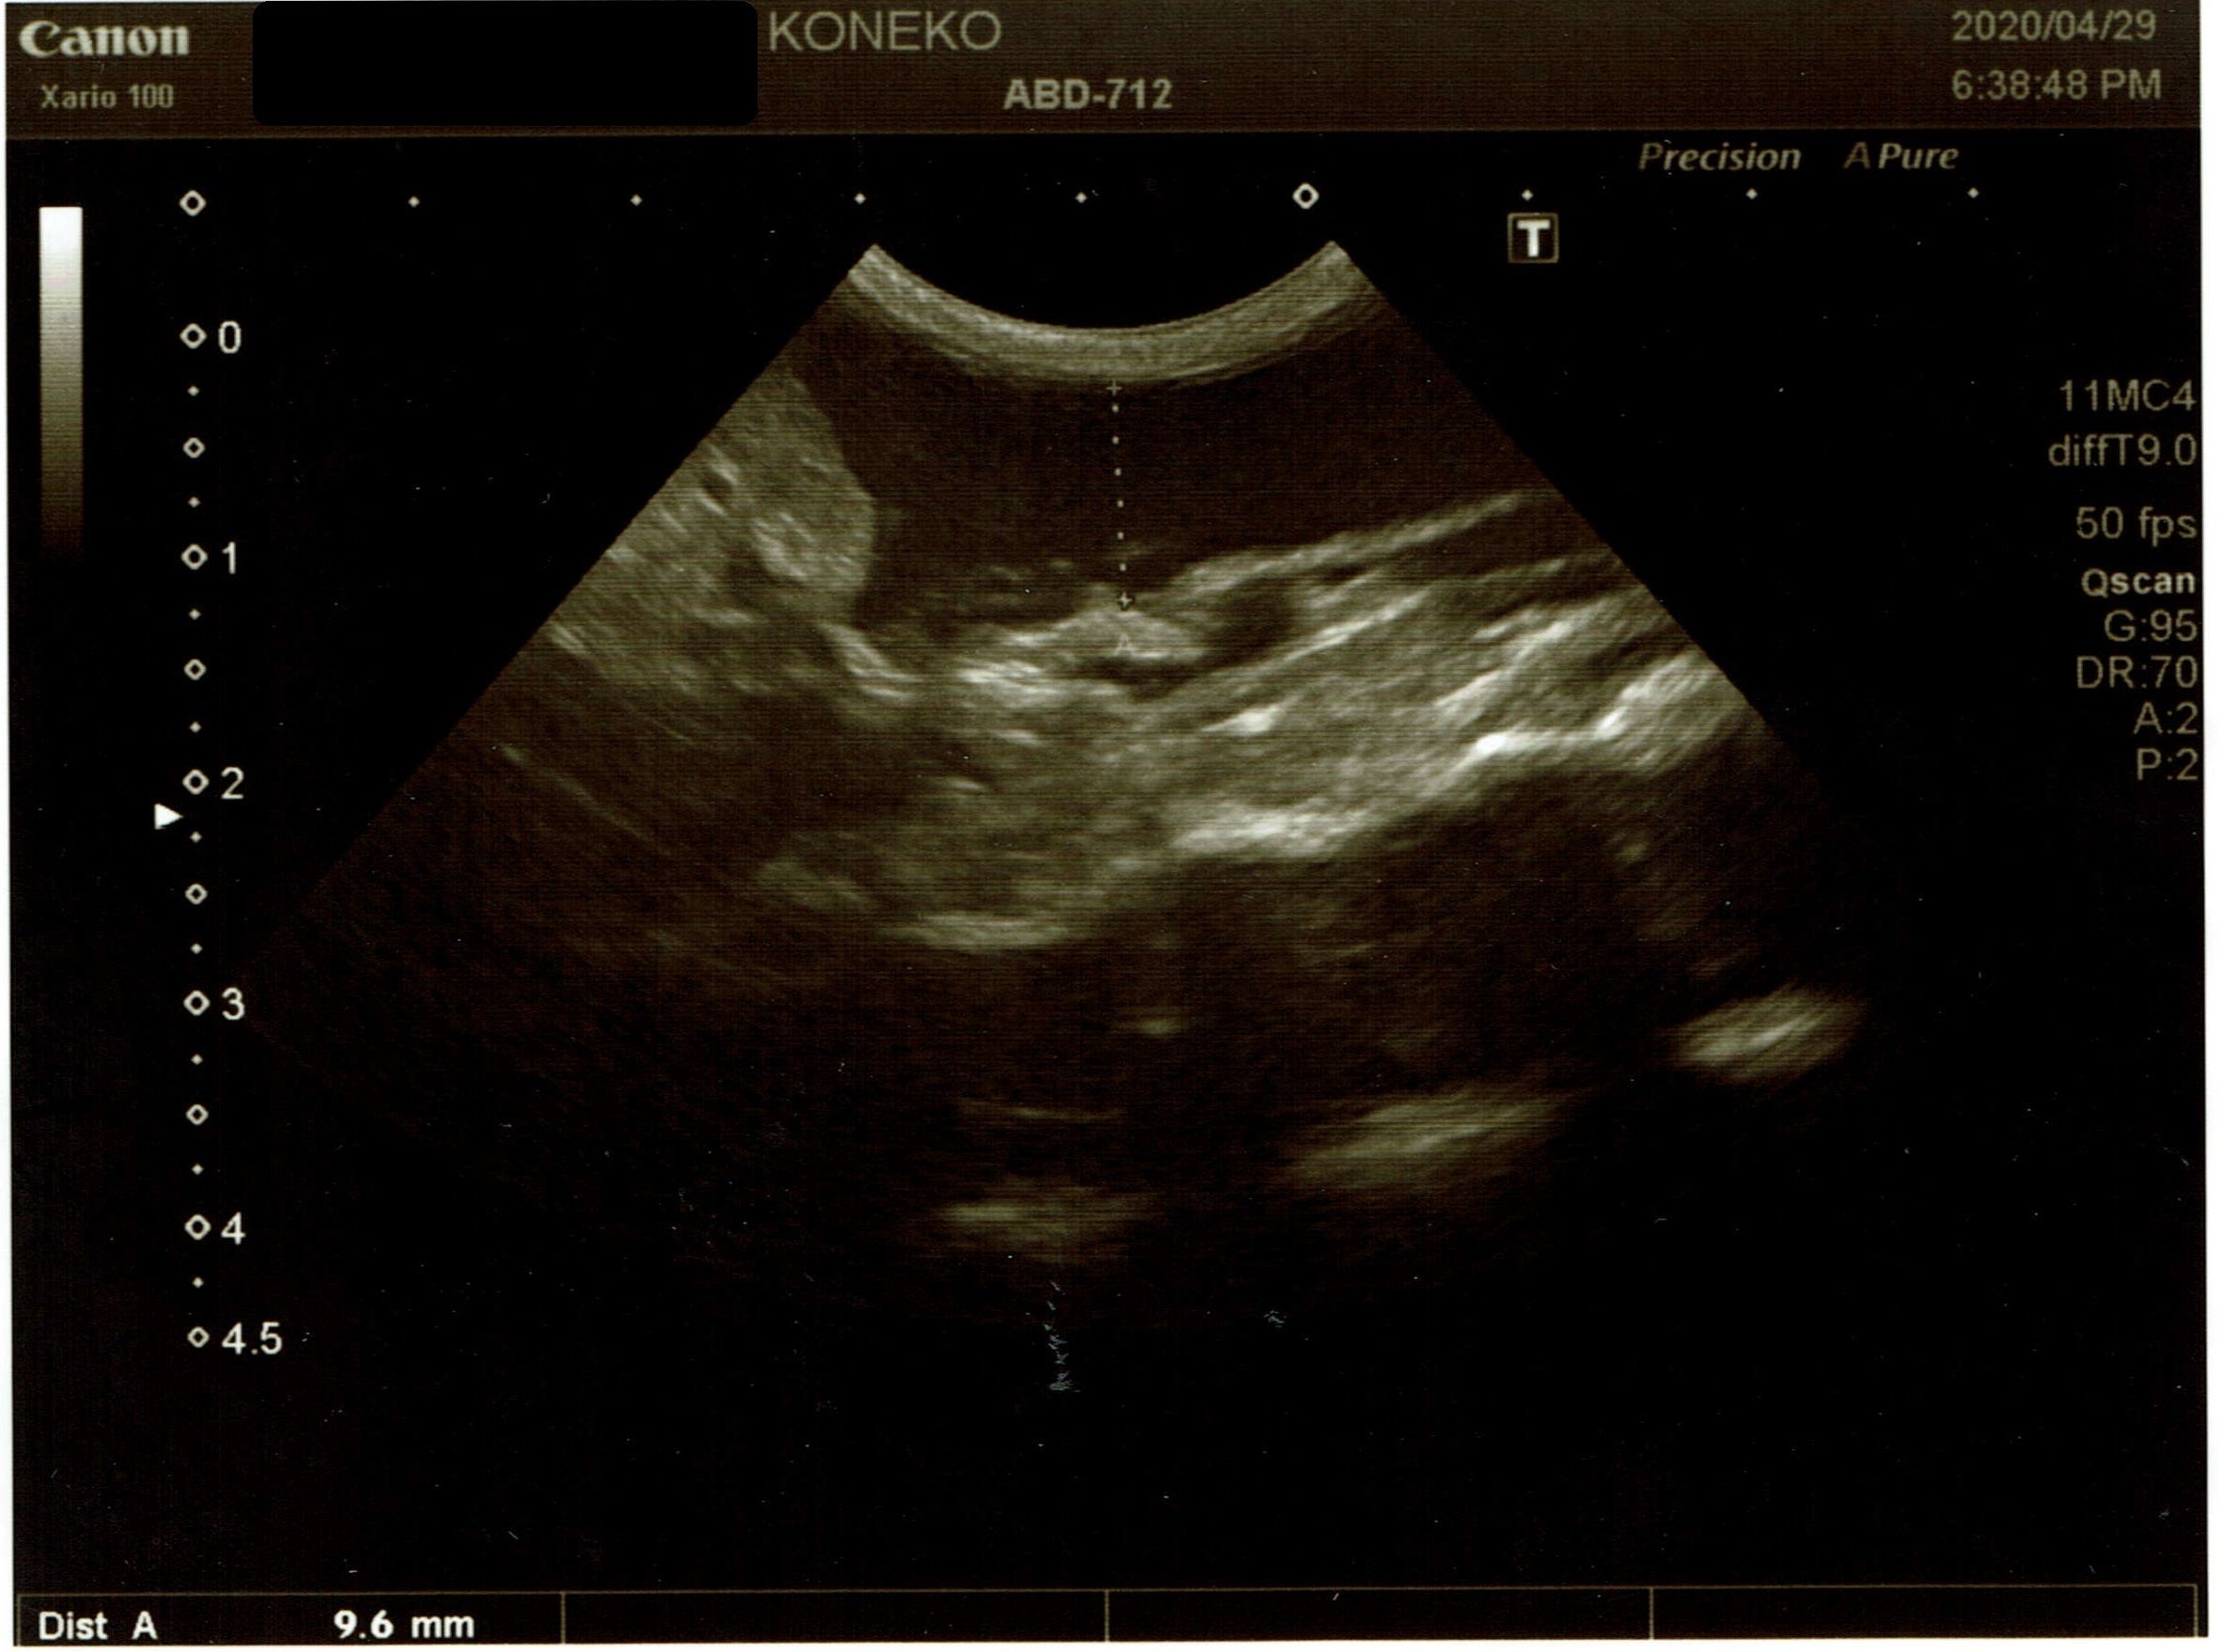

4月29日

ただのおデブちゃんか、FIPか診てもらおうとA動物病院へ。

↑

1〜2㎝の腹水貯留あり腹部エコーと腹水穿刺の結果、恐らくウェットタイプのFIPで間違いないだろうと。

腹水の検体を検査に出して、猫コロナウイルス陽性の結果であれば、FIP確定だと説明されました。